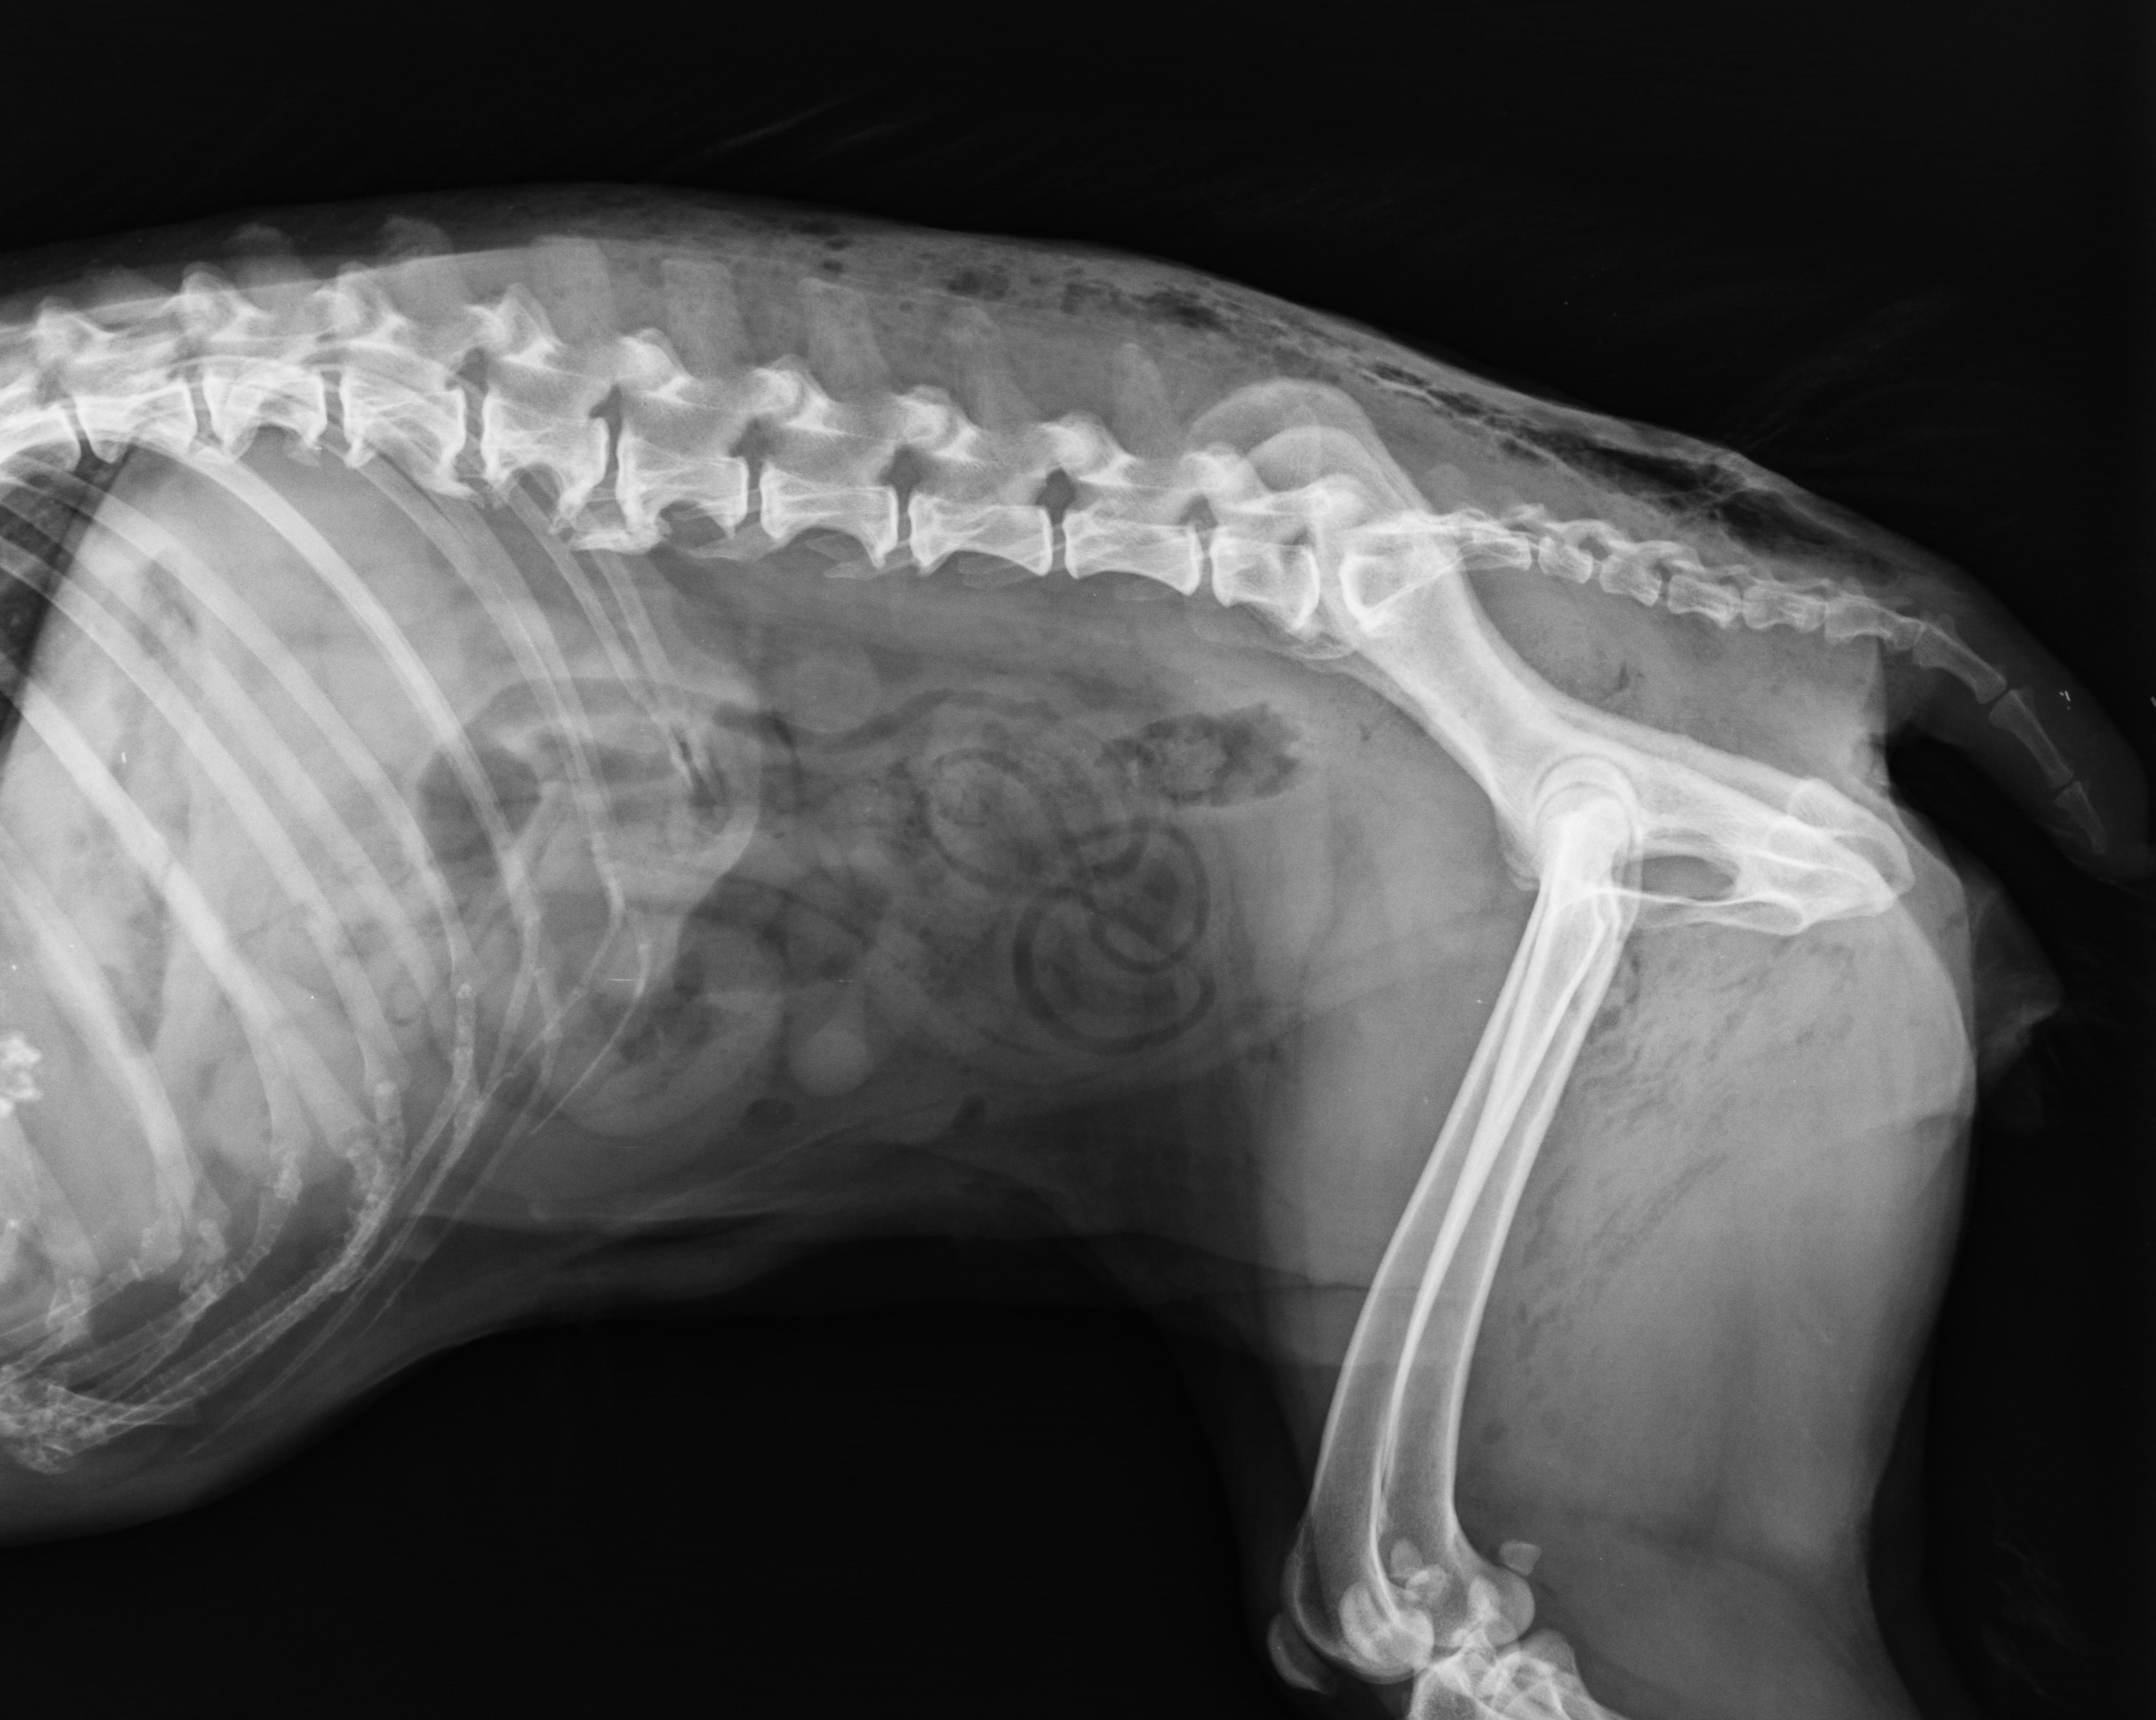

Spinal Arthritis

02/07/2023

Spinal osteoarthritis is a very common problem in companion animals however it is one of the most under-recognized causes of pain for dogs and cats. Animals with back pain may show signs of lameness a...

Osteoarthritis Awareness And Recognition In Dogs And Cats

01/31/2023

The pain of arthritis (osteoarthritis or OA) adversely impacts the lives of dogs and cats as well as the activities we can share in with them. But there is hope for these animals - beyond a prescripti...